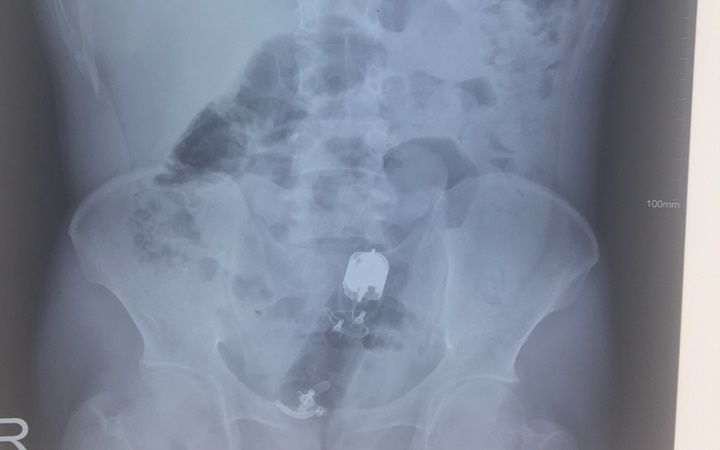

Chụp X-quang hoặc CT Scan để phát hiện dị vật và loại trừ khả năng tổn thương đường ruột.

Click vào ảnh để xem 3 hình ảnh minh họa